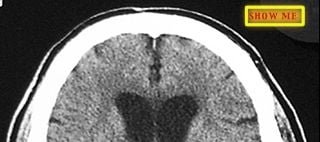

Identify areas of ischemia.